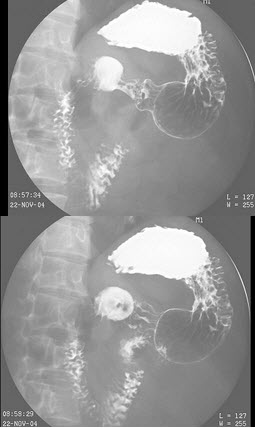

4、单项选择题

男,78岁,吞咽困难,梗阻感1年,结合图像,最可能的诊断为()

A.正常食管下段

B.食管癌

C.贲门失弛缓

D.贲门癌

E.胃癌

27、单项选择题  肺门舞蹈征最多见于哪种先天性心脏病()

A.动脉导管未闭

B.室间隔缺损

C.房间隔缺损

D.法洛四联征

E.艾森曼格综合征